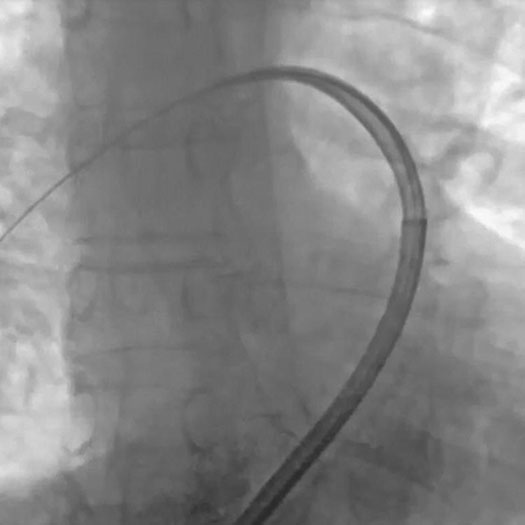

Above: Select + Catheter H1 tip shape

The company also announced a CE Mark for its Select™ + Catheter, effectively completing Penumbra’s VTE thrombectomy platform, from access to aspiration. Select + is engineered for the pulmonary anatomy, creating a seamless transition and designed for safe access through the heart.